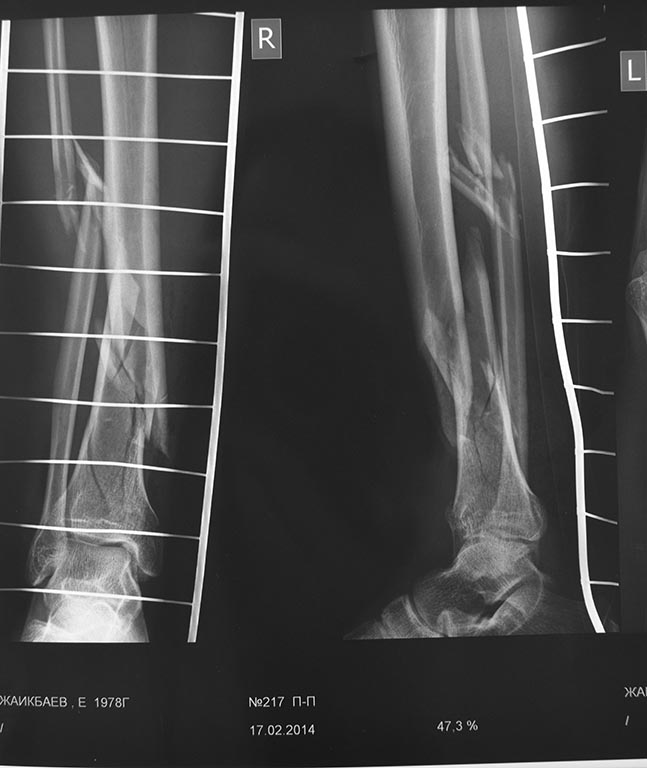

Коллеги поступает пациент с открытым оскольчатым переломом костей голени

рана по медиальной поверхности 1,0х0,5 см, без признаков инфицирования. Таких переломов мы всегда синтезировали аппаратом Илизарова. В данном случае можно ли БИОС?

Судя по рентгенограммам имеет место перелом пилона. БИОС в этом случае не имеет преимуществ и не подходит, как метод фиксации. Я бы выполнил Rg-контроль в динамике и КТ, чтобы иметь полное представление о состоянии суставной поверхности большеберцовой кости.

Что касается раны, то знания только лишь ее размеров недостаточно для выбора тактики лечения. Каково состояние мягких тканей в ее окружении, на каком протяжении была отслойка, условия (характер загрязнения) получения открытого перелома?